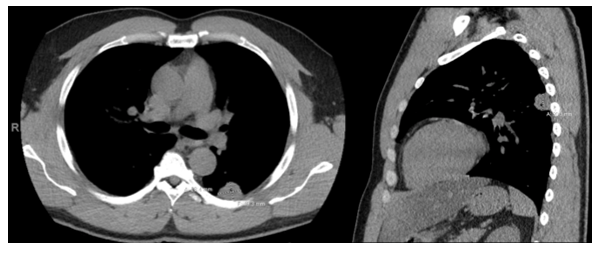

The Gram stain of the driveline exit site was unremarkable, with no organisms and few neutrophils seen. Aerobic cultures yielded a light amount of gram positive cocci in addition to mixed skin flora. Colonies were small, and weakly beta hemolytic on blood agar (Image 1A). This organism was catalase- and coagulase-positive, and definitively identified as Staphylococcus aureus by MALDI-TOF MS. Susceptibility testing was performed by broth microdilution, where the organism was determined to be a vancomycin-intermediate Staphylococcus aureus (VISA, MIC=4, Image 1C). Due to the unusual nature of the result, it repeated and confirmed by E-test (Image IB) in our laboratory, and independently verified at our contract reference laboratory. The isolate was also referred to the Texas State Public Health Laboratory where the vancomycin-intermediate phenotype was again confirmed. This isolate was also daptomycin non-susceptible, but remained susceptible to oxacillin, trimethoprim/sulfamethoxazole, linezolid, rifampin, and clindamycin.